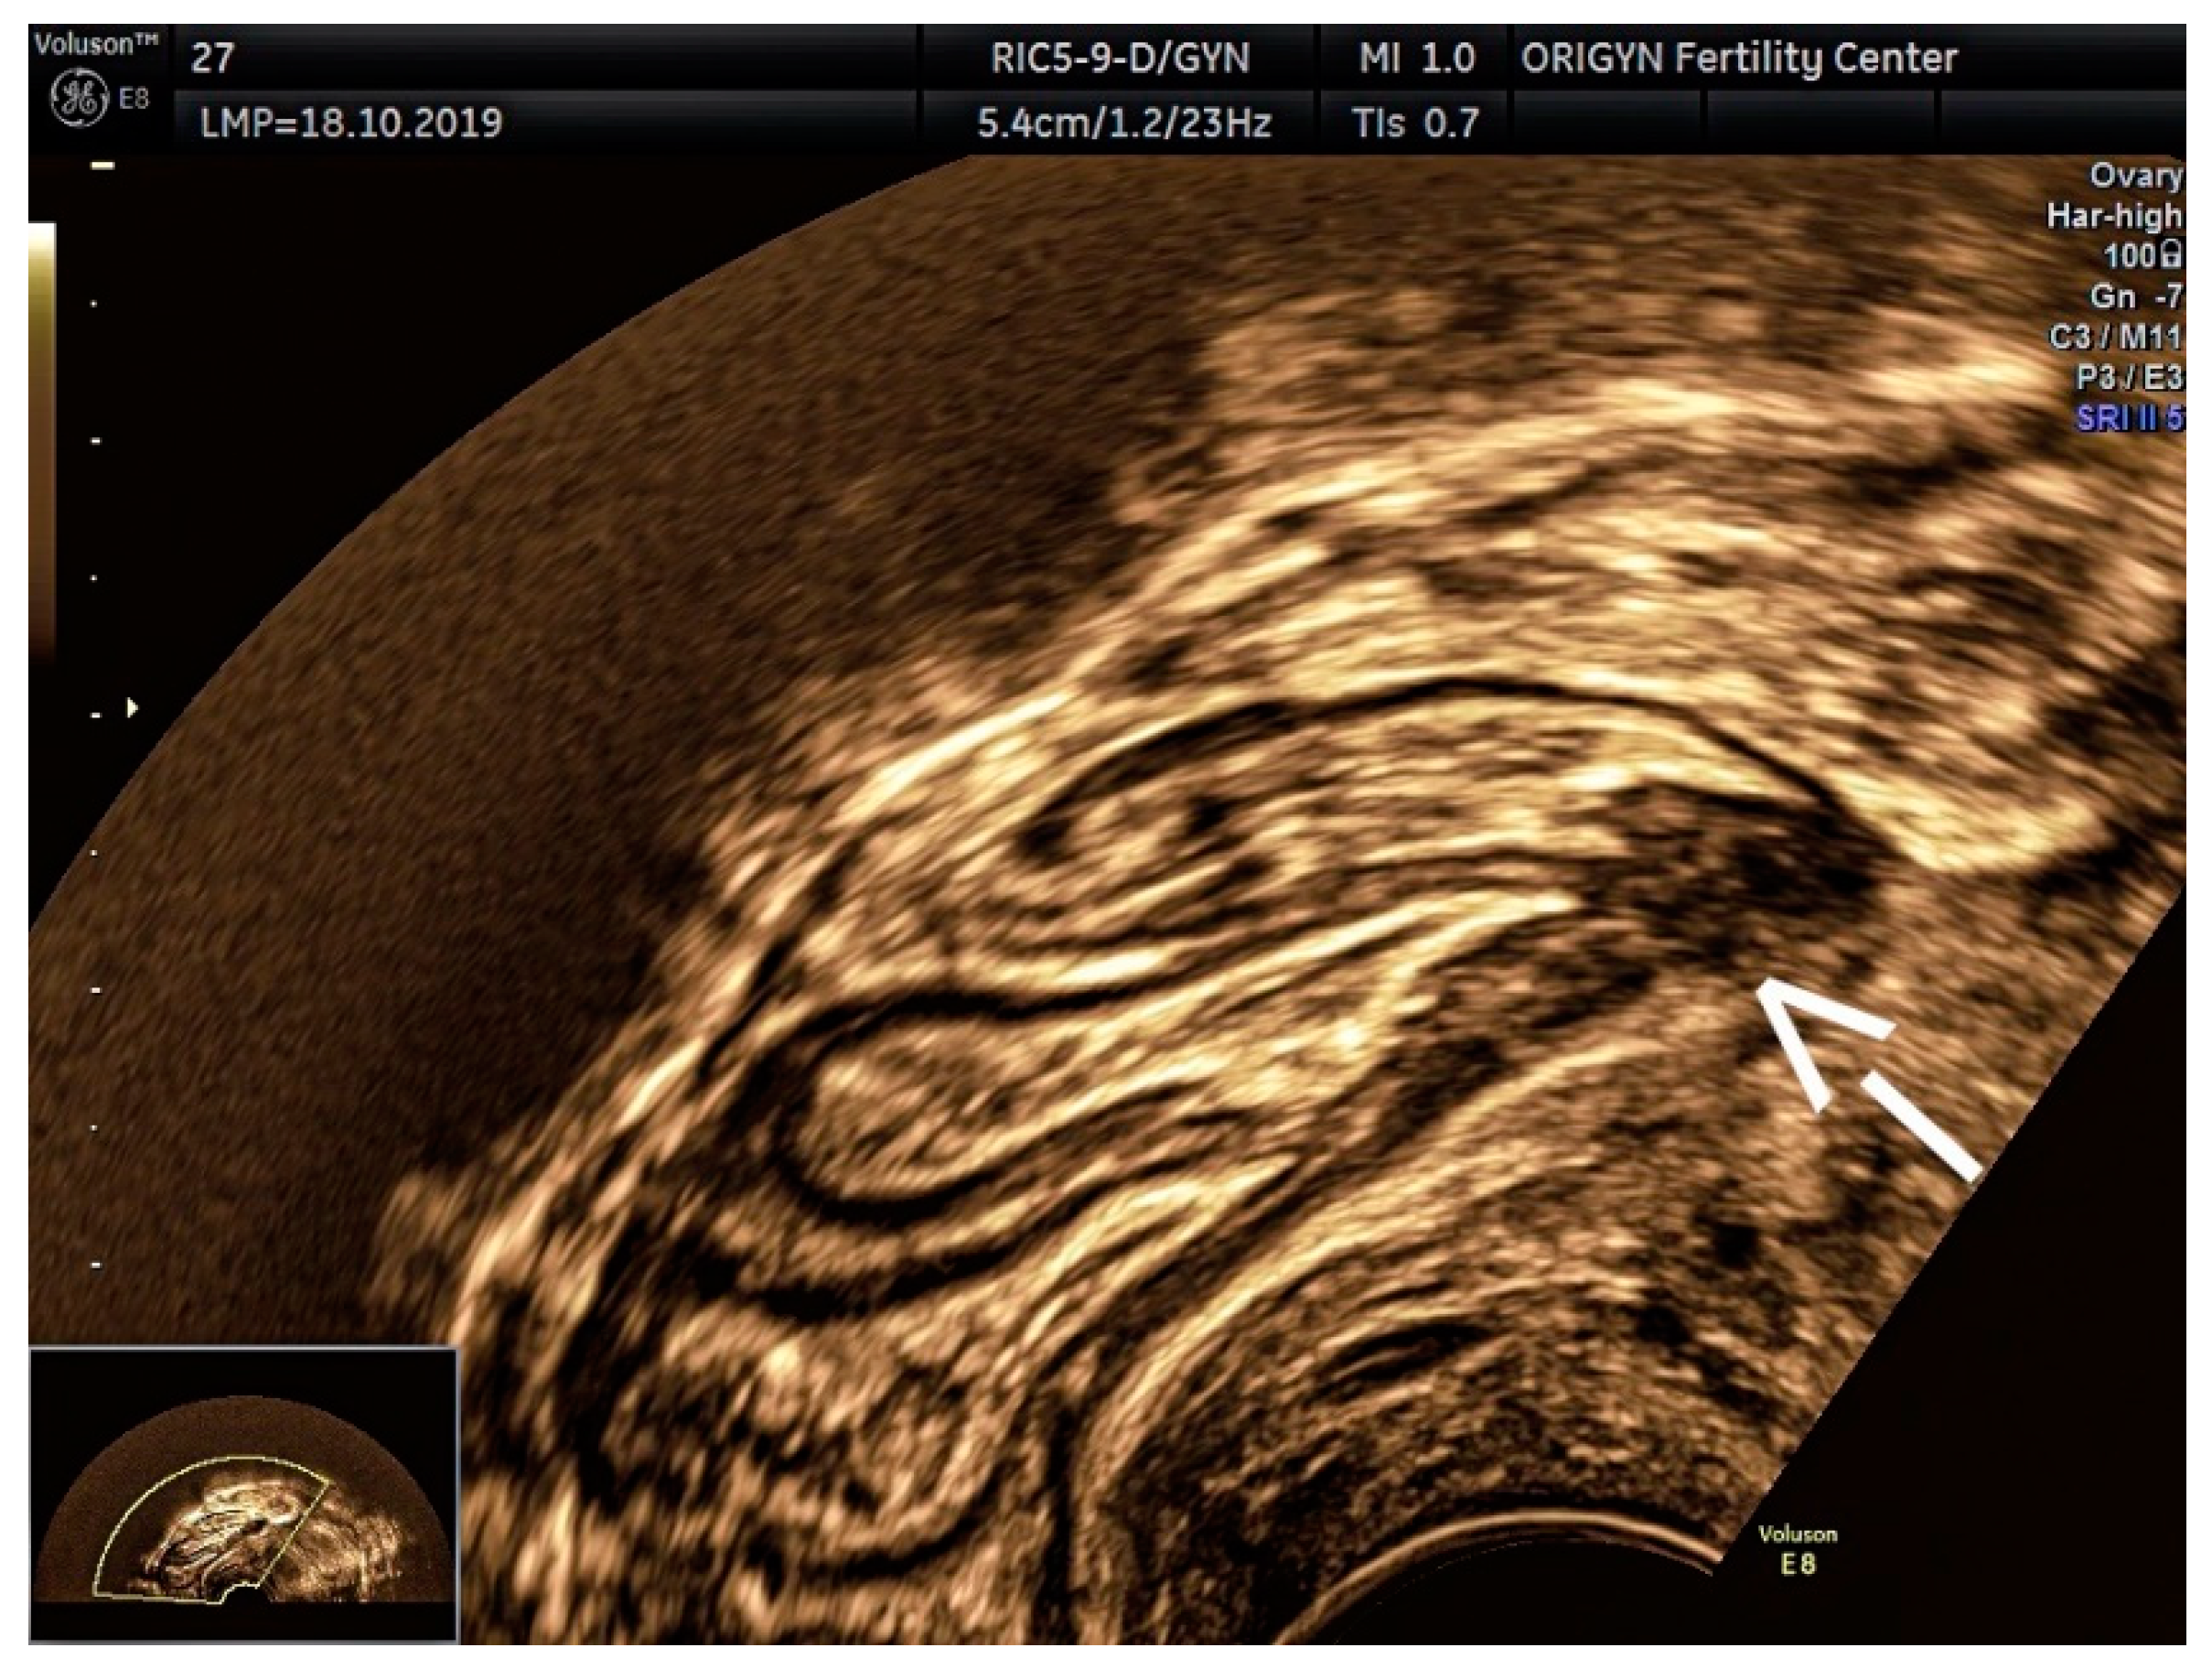

3.3. Posterior Compartment